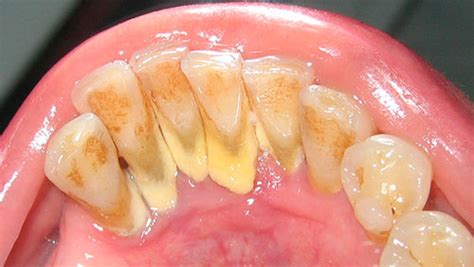

El sarro es, por tanto, resultado del endurecimiento de esa placa bacteriana no retirada. Forma un recubrimiento blanquecino o amarillento en la base de los dientes, en especial en los dientes inferiores anteriores por el lado de la lengua y en los molares superiores por el lado de la mejilla.

El sarro tiene la apariencia de una costra gruesa que cubre los dientes, sobre todo la parte trasera de las piezas delanteras inferiores, que es una zona más difícil de limpiar. También puede formarse entre las piezas dentales y el borde de las encías.

Inicialmente su color es blanquecino, pero se mancha con facilidad y puede adquirir un tono amarillento o amarronado. Asimismo, puede presentarse acompañado de hinchazón y enrojecimiento de las encías, cuadro conocido como gingivitis.

En función de su localización, el sarro puede ser:

- Supragingival: Se acumula en la superficie visible de los dientes y encías.

- Subgingival: Se localiza por debajo de la línea de la encía, por lo que es más difícil de percibir.